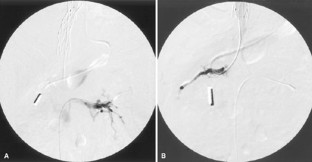

Percutaneous Stent Placement as Treatment of Renal Vein Obstruction Due to Inferior Vena Caval Thrombosis

A patient who had undergone his third orthotopic liver transplantation nearly 9 years prior to presentation developed worsening hepatic and renal function, as well as severe bilateral lower extremity edema. Magnetic resonance imaging demonstrated vena caval thrombosis from the suprahepatic venous anastomosis to the infrarenal inferior vena cava, obstructing the renal veins. This was treated by percutaneous placement of metallic stents from the renal veins to the right atrium. At 16 months clinical follow-up, the patient continues to do well.

Figure 2